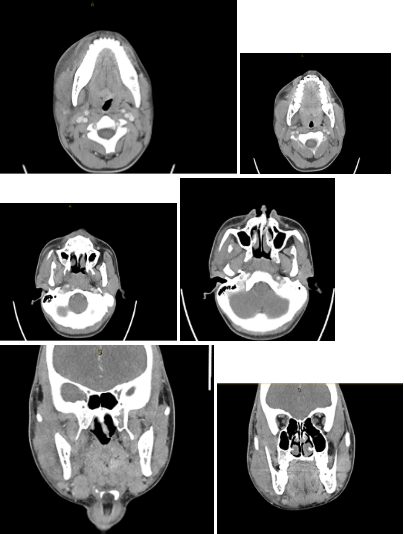

CT Maxillofacial soft tissue views of patient in Case 2